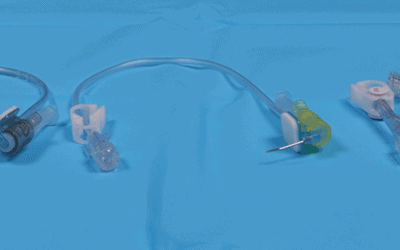

Tras iniciar la exploración del capital venoso, mediante el método RaPeVA (desarrollado por el grupo GAVeCeLT), podemos aplicar el doppler color para identificar y diferenciar las estructuras arteriales y venosas.

Tras iniciar la exploración del capital venoso, mediante el método RaPeVA, podemos aplicar el doppler espectral para identificar y diferenciar las estructuras arteriales y venosas.

- Mauro Pittiruti y Giancarlo Scoppettuolo, Manual GAVeCeLT para PICC y Midlines, indicaciones, inserción y mantenimiento – 2016